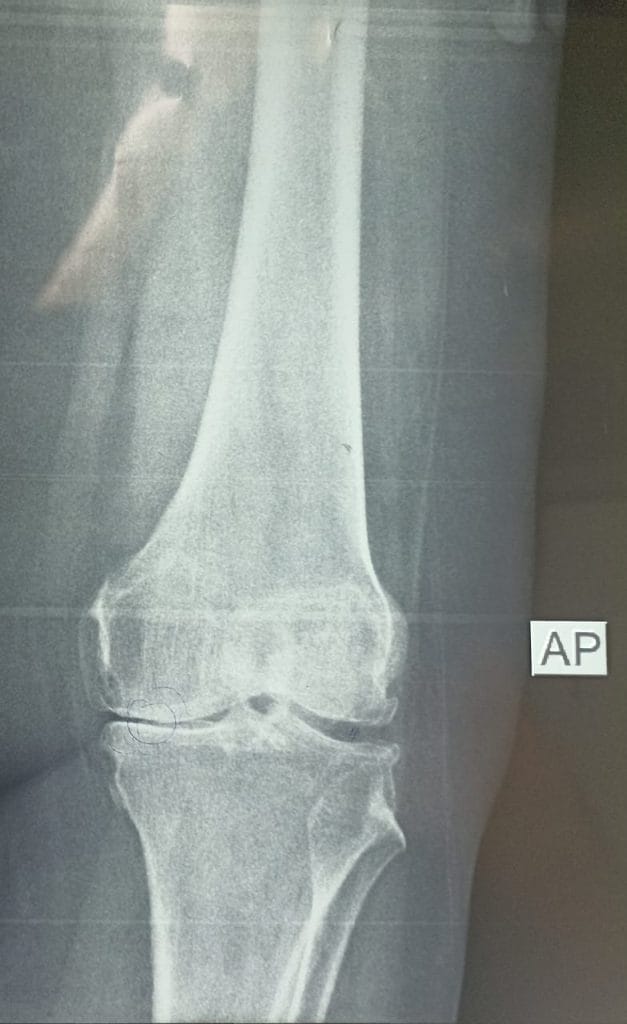

بتأريخ 2022/10/31 راجعت المريضة استشارية العظام والكسور في مستشفى ابن سينا التدريبي وكانت تعاني من ألم شديد في مفصل الركبه اليسرى ، وبعد اجراء الفحوصات السريرية والمختبرية والشعاعية تبين انها تعاني من سوفان شديد و تحدد في مفصل الركبه اليسرى .